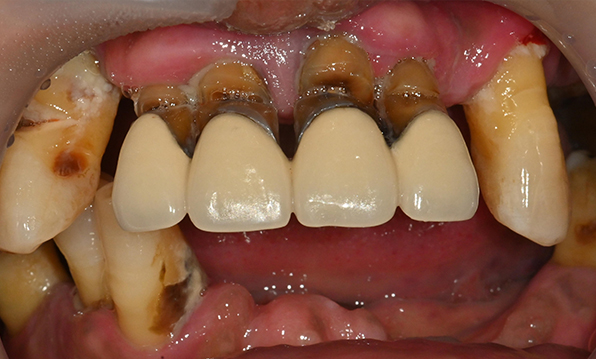

전체 임플란트가 필요한 경우

치아가 얼마 남아있지 않은 경우

치주질환이 심해, 치아가 있더라도 제 기능을 하지 못하는 경우

틀니 사용이 불편한 경우

치료기간 : 2021.04.12~2021.09.15